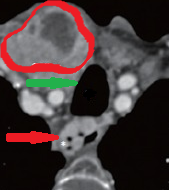

Chest-neck CT. Red outline: enlarged right thyroid lobe. Green arrow: mild pressure on the trachea. Red arrow: downhill esophageal varices (Courtesy Dr. V. Penopoulos)